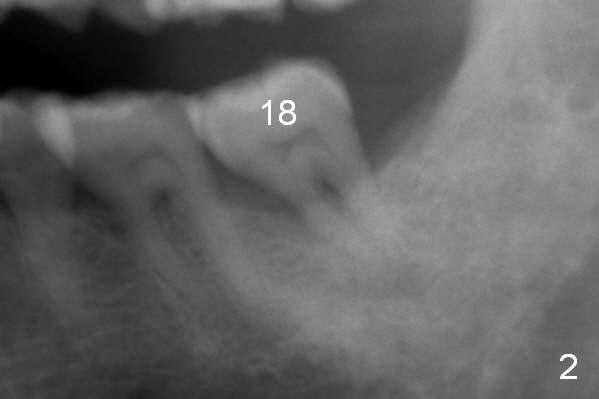

A 59-year-old man has history of chronic periodontitis (Fig.1 (taken in 2005), 2 (2014), 3 (2016)) involving the tooth #18. The bone loss may be complicated by bruxism. Large crown vs. narrow roots contributes to severe bone loss. An implant should be as long as possible and placed as coronally as possible to tackle crown/implant ratio issue. To prevent peri-implantitis, the implant may have to be placed deep. It appears that the bone height is more favorable mesially than distally (Fig.3). After extraction of the supraerupted and loose tooth (Fig.4; no Antibiotic), explore the socket to determine the favorite osteotomy site, most likely the mesial socket, lingually.